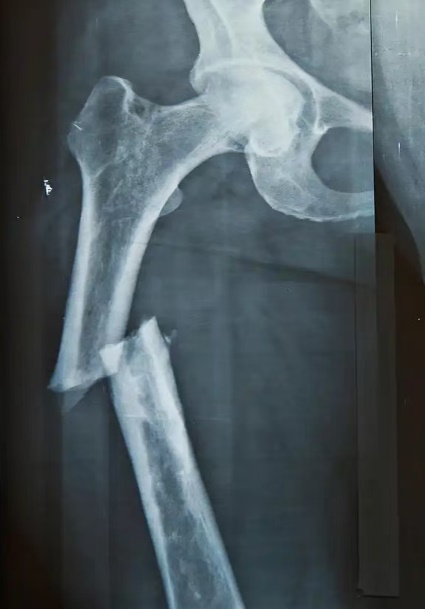

下肢骨折术后如何“走”出迷茫?

下肢骨折在日常生活中颇为常见,其成因繁杂多样,无论是意外事故,还是运动过程中的不慎损伤等,都有可能导致下肢骨折情况的发生。术后康复这一环节对于下肢功能能否顺利恢复以及生活质量能否有效提升,有着至关重要的影响,可谓举足轻重。本文将为您介绍下肢骨折术后康复的相关知识,帮助您更好地了解这一重要阶段,助力康复之路。